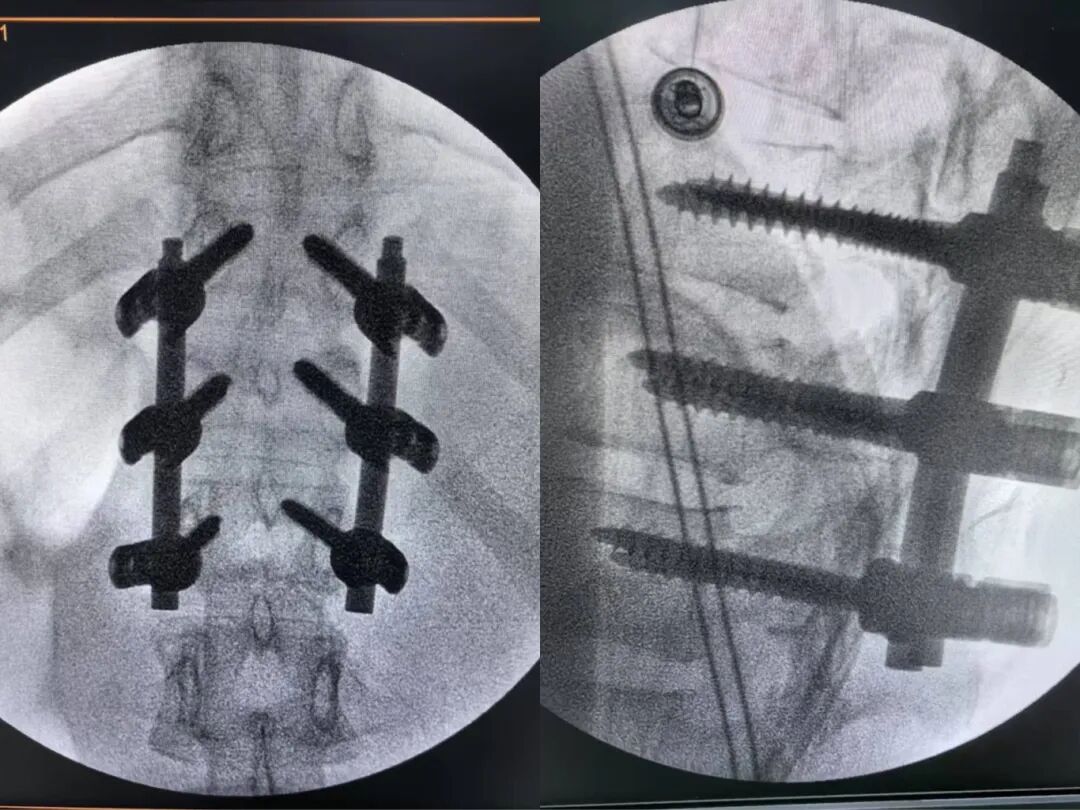

△胸椎爆裂骨折复位内固定技术

小杨母亲的朋友此前在青岛医院顺利完成了颈椎和腰椎手术,将青岛医院推荐给了小杨。出于对医院和朋友的信任,一家人连夜购买机票,跨越580公里奔赴青岛。“最好手术,长期拖着可能造成永久性驼背和慢性腰背疼痛,甚至造成脊髓损害。”李强主任说。

完善检查后,脊柱外科团队为患者实施了胸椎骨折切开复位内固定术,仅用7公分切口就完成了高难度复位固定。术后第三天,小杨已能戴着护具下床活动,目前已顺利出院。